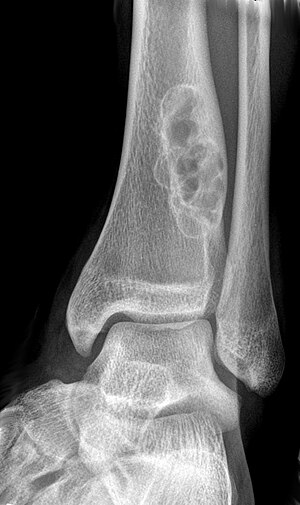

Chondroblastoma[2] Chondroblastoma-distal-femur-2-4.jpg

Cancerous (Chondrosarcoma) Conventional chondrosarcoma grade I (axial skeleton)-III[1][2] Chondrosarcoma (Radiopaedia 23076).jpg